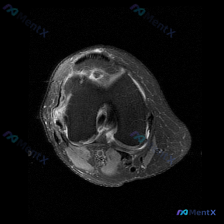

看到一份很有讨论价值的膝关节MRI病例,整理了影像发现和分析思路,和大家一起交流。 病例影像基本信息 这是一份膝盖MRI的轴位T2加权图像,扫描层面位于髌股关节滑车沟层面,可观察到以下明确异常: 1. 髌骨改变:髌骨后方关节软骨信号不均匀、局部T2高信号,软骨形态不规则、厚度变薄;髌骨边缘骨质可见高...

看到一份膝关节轴位MRI的读片资料,软骨异常是核心发现,整理了影像特征和完整分析思路,和大家分享讨论。 一、影像基本信息 这是膝关节髌股关节层面的脂肪抑制序列MRI(PD-FS或T2-FS),图像特征: 1. 髌骨、股骨皮质低信号,骨髓脂肪信号正常 2. 核心异常:髌骨后方关节软骨信号不均匀,局部高...

看到这个膝关节MRI的病例,整理了完整的影像表现和分析思路,分享给大家一起讨论。 一、病例基本影像信息 这是一份膝盖MRI T2序列轴位图像,扫描层面位于髌股关节层面,可见髌骨与股骨滑车关节面,评估结果如下: 1. 关节软骨:髌骨后方关节软骨为低信号带,髌股关节外侧面可见不均匀高信号改变,提示软骨磨...